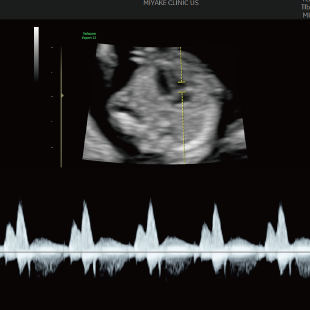

Voluson Expert 22®(GEHealthcare)という産婦人科領域におけるハイエンド超音波診断装置を使用しています。 従来機種と比べ、より高精細な画像描出性能と高度な解析機能を備えており、 胎児の発育や形態をより詳細に観察することが可能です。

通常の妊婦健診で行う超音波検査では、主に胎児発育(推定体重)、羊水の量、胎児の向きを確認しています。一方で健診の限られた時間内では、胎児を詳細かつ系統的に評価することが難しい場合があります。当院で行っている胎児超音波スクリーニングとは、高性能な超音波検査機器を用いて胎児の発育や形態(からだの構造)をより詳しく観察し、胎児の状態を丁寧に評価する検査です。 出産前に赤ちゃんの状態をより詳しく知りたいという患者さんのご希望にお応えするため、当院では超音波検査士*および超音波専門医・指導医**が胎児超音波スクリーニングを担当します。